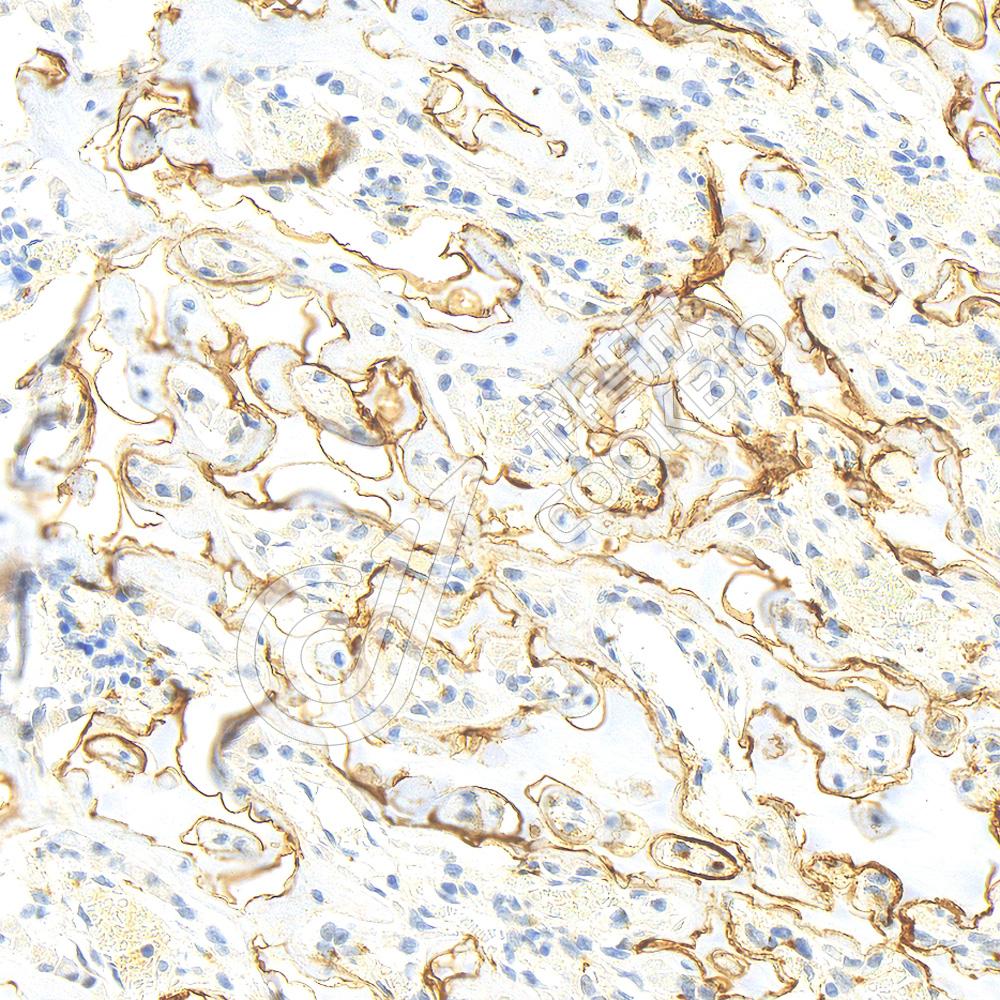

IHC检测Osteopontin蛋白(货号 K2366984).

样品: 大鼠骨, 4%多聚甲醛 (货号KSG1101) 固定12-24小时.

抗原修复: 柠檬酸抗原修复液(干粉, pH 6.0) (KSG1201), 高压锅均匀喷气计时2分钟.

—抗: 1: 1400稀释, 4℃ 孵育过夜.

二抗: S-vision免疫组化多聚二抗(山羊抗小鼠), 即用型(货号KB3903), 室温孵育20分钟.

样品: 大鼠股骨, 4%多聚甲醛 (货号KSG1101) 固定12-24小时.